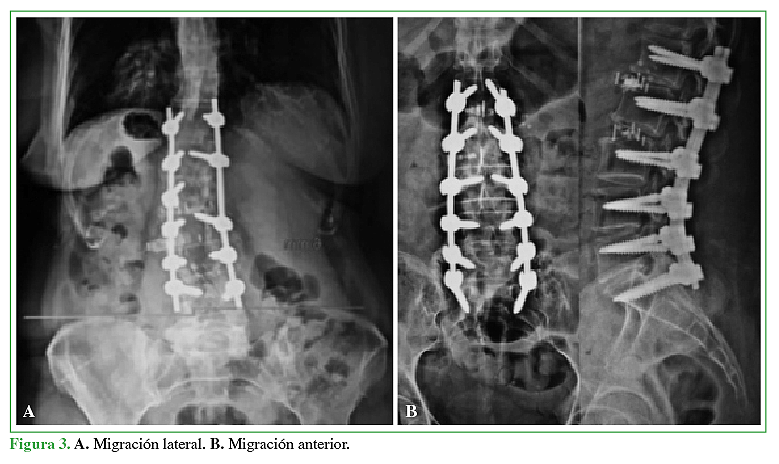

16. Daffner SD, Wang JC. Migrated XLIF cage: case report and discussion of surgical technique. Orthop. 2010,33:518.

17. Towers WS, Kurtom KH. Stand-alone LLIF lateral Cage Migration: Acase report. Cureus 2015, 7(10) e347.